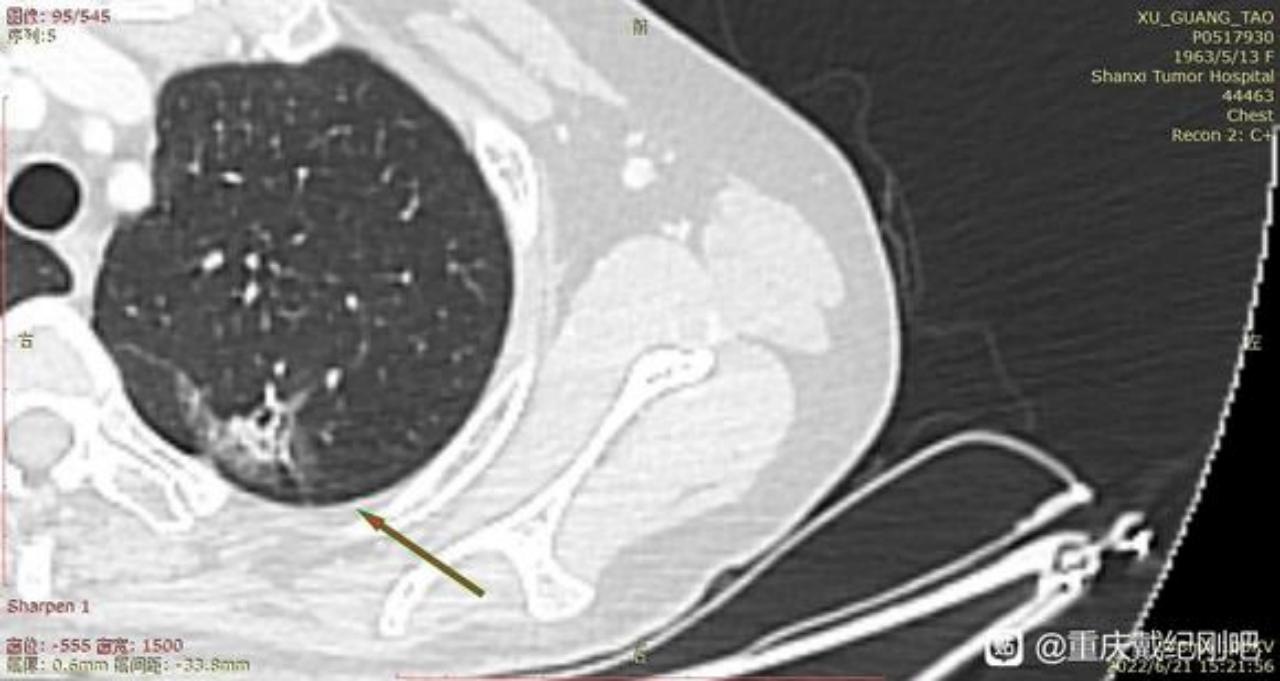

主任前段时间已经麻烦过您了,术后病例确实跟您的判断一样,左肺上叶结节为早期肺腺癌(腺泡型)。当时我们医生先是进行了楔形切除,中间又出来谈话进行了叶切。(患者我母亲,59岁女性,不抽烟喝酒)现在术后病例出来了:腺泡型肺腺癌、大小2cm*1.5cm*1cm,支气管、淋巴结未见累计。

3、主任,根据您之前判断,右肺下页的0.7毫米磨玻璃结节至少是微浸润。现在医生给切了左肺上叶,后面手术多久能进行啊?是不是难度很大了?